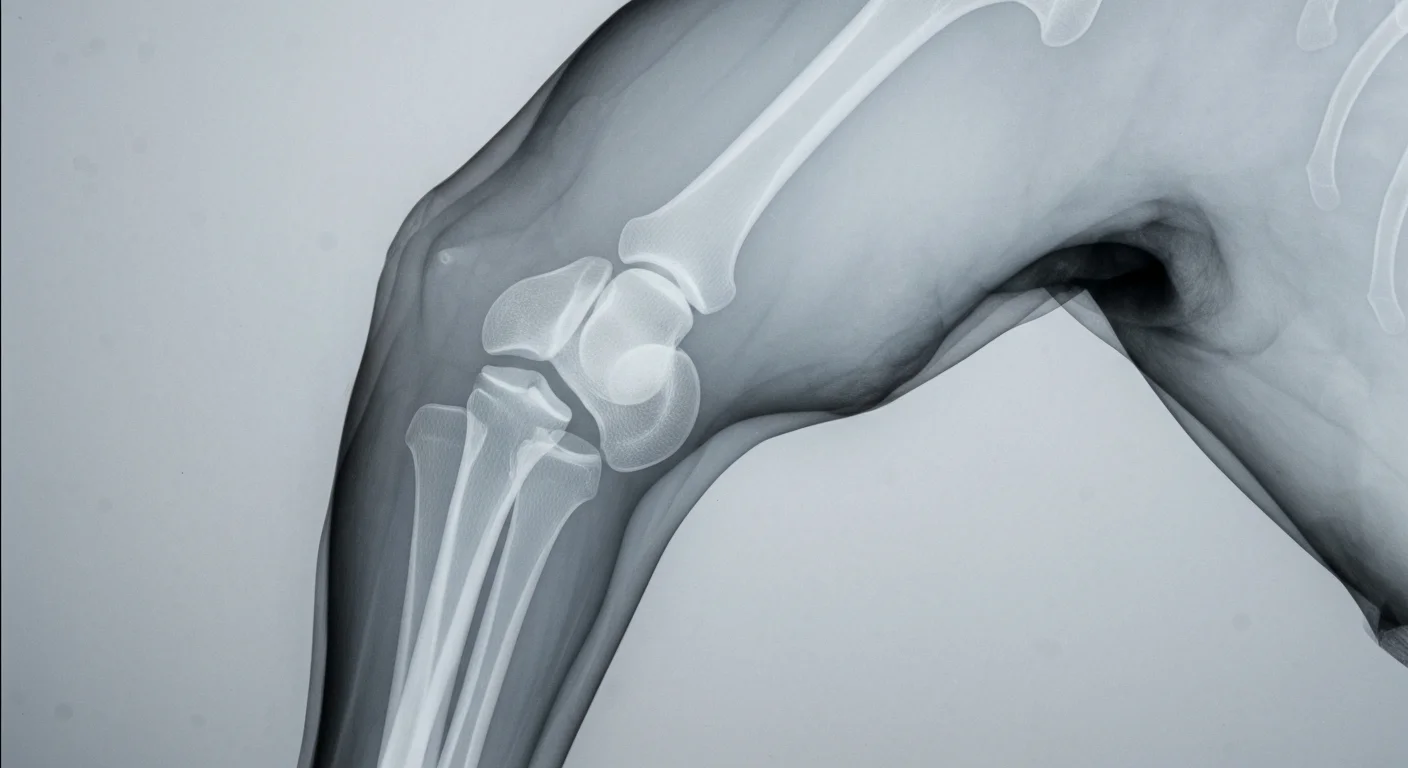

OFA elbow certification X-ray positioning for Labrador Retriever health screening